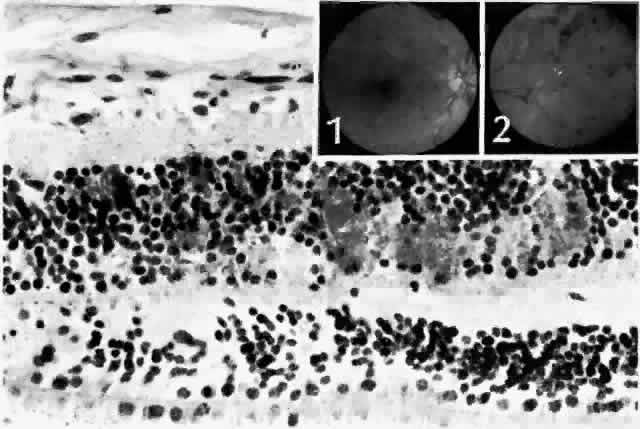

Hard exudates clinically appear as shiny yellow deposits (see Fig. 5; Color Fig. D). When they surround a microaneurysm in a circular pattern, the condition is called circinate retinopathy. Histologically, the deposits accumulate at the level of the outer plexiform layer (Fig. 8, Color Fig. E) and consist of lipids, complex carbohydrates, and proteins, as demonstrated histochemically. Hard exudates are normally asymptomatic unless they involve the macula, where they cause a drop in visual acuity. If a leaking microaneurysm can be identified on fluorescein angiography, laser photocoagulation can obliterate it. Over time, the fluid is resorbed, and sometimes visual acuity can improve.40

Fig. 8. Hard or waxy exudates. Retinal exudates accumulate in the outer plexiform (Henle's fiber) or in inner nuclear (bipolar cell) layers. Note that in this case the middle limiting membrane separates the layers. Inset. Fundus appearance of a moderate background diabetic retinopathy. (Main figure, H&E, × 220)

In some patients, the cystoid spaces can coalesce, forming lamellar or full-thickness macular holes.42 Other nonproliferative changes include intraretinal hemorrhages. Flame-shaped hemorrhages occur in the nerve fiber layer, and dot-blot hemorrhages occur in deeper retina, in the outer plexiform and inner nuclear layers (Fig. 9).

Fig. 9. Dot and blot hemorrhages consist of small collections of blood in the inner nuclear and outer plexiform layers of the retina. Insets. Fundus appearance of dot (1) and blot (2) hemorrhages, respectively. (Main figure, H&E, × 260)